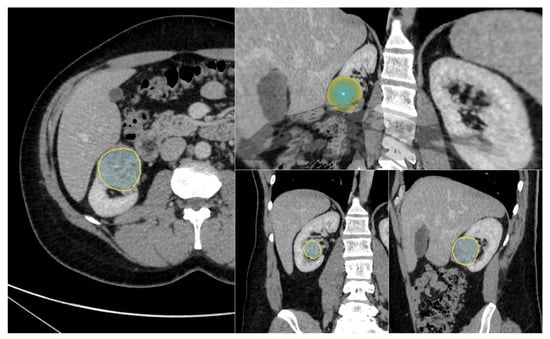

All Digital Imaging and Communication in Medicine images were anonymized. Segmentation was performed by C.G. using SOPHiA DDM for Radiomics v2.1.21 (SOPHiA GENETICS, Saint-Sulpice, Switzerland). In accordance with previous studies, nephrographic phase images were segmented due to their favorable tumor/renal parenchymal contrast. First, the slice on which the tumor was clearest (axial, coronal or sagittal plane) was chosen, and the tumor contours were precisely drawn by hand. Next, a volumetric model of the tumor was constructed using a deformation algorithm. If necessary, the user could manually adjust the semi-automatically obtained contours of the lesion. Each 3D segmentation process took approximately 20 min. The user interface of the segmentation software is shown in Figure 3.

Figure 3. Three-dimensional (3D) segmentation software interface for a clear cell RCC. Tumor segmentation on 2D slice at nephrographic phase (yellow outline, left), with corresponding 2D segmentations on coronal and sagittal plans (lower right), and a volumic model of the 3D segmentation (upper right) used for radiomic features extraction.